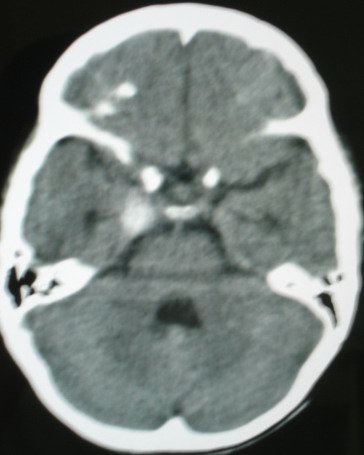

m/8y/,右侧眼睑下垂数日,发育良好,无外伤史,无头痛、恶心、呕吐,学习成绩良好。

ct意见:1、颅内血管畸形。2、右侧海绵窦血管瘤(颈内动脉海绵窦段动脉瘤)。3、脑萎缩。4、建议mr或dsa.

增强片